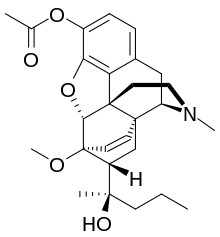

Several semi-synthetic opioids were developed in Germany in the 1910s. The first, oxymorphone, was synthesized from thebaine, an opioid alkaloid in opium poppies, in 1914.[228] Next, Martin Freund and Edmund Speyer developed oxycodone, also from thebaine, at the University of Frankfurt in 1916.[229] In 1920, hydrocodone was prepared by Carl Mannich and Helene Löwenheim, deriving it from codeine. In 1924, hydromorphone was synthesized by adding hydrogen to morphine. Etorphine was synthesized in 1960, from the oripavine in opium poppy straw. Buprenorphine was discovered in 1972.[228]

The first fully synthetic opioid was meperidine (later demerol), found serendipitously by German chemist Otto Eisleb (or Eislib) at IG Farben in 1932.[228] Meperidine was the first opiate to have a structure unrelated to morphine, but with opiate-like properties.[199] Its analgesic effects were discovered by Otto Schaumann in 1939.[228] Gustav Ehrhart and Max Bockmühl, also at IG Farben, built on the work of Eisleb and Schaumann. They developed "Hoechst 10820" (later methadone) around 1937.[230] In 1959 the Belgian physician Paul Janssen developed fentanyl, a synthetic drug with 30 to 50 times the potency of heroin.[211][231] Nearly 150 synthetic opioids are now known.[228]

Opium alkaloids and derivatives

Phenanthrenes naturally occurring in (opium):